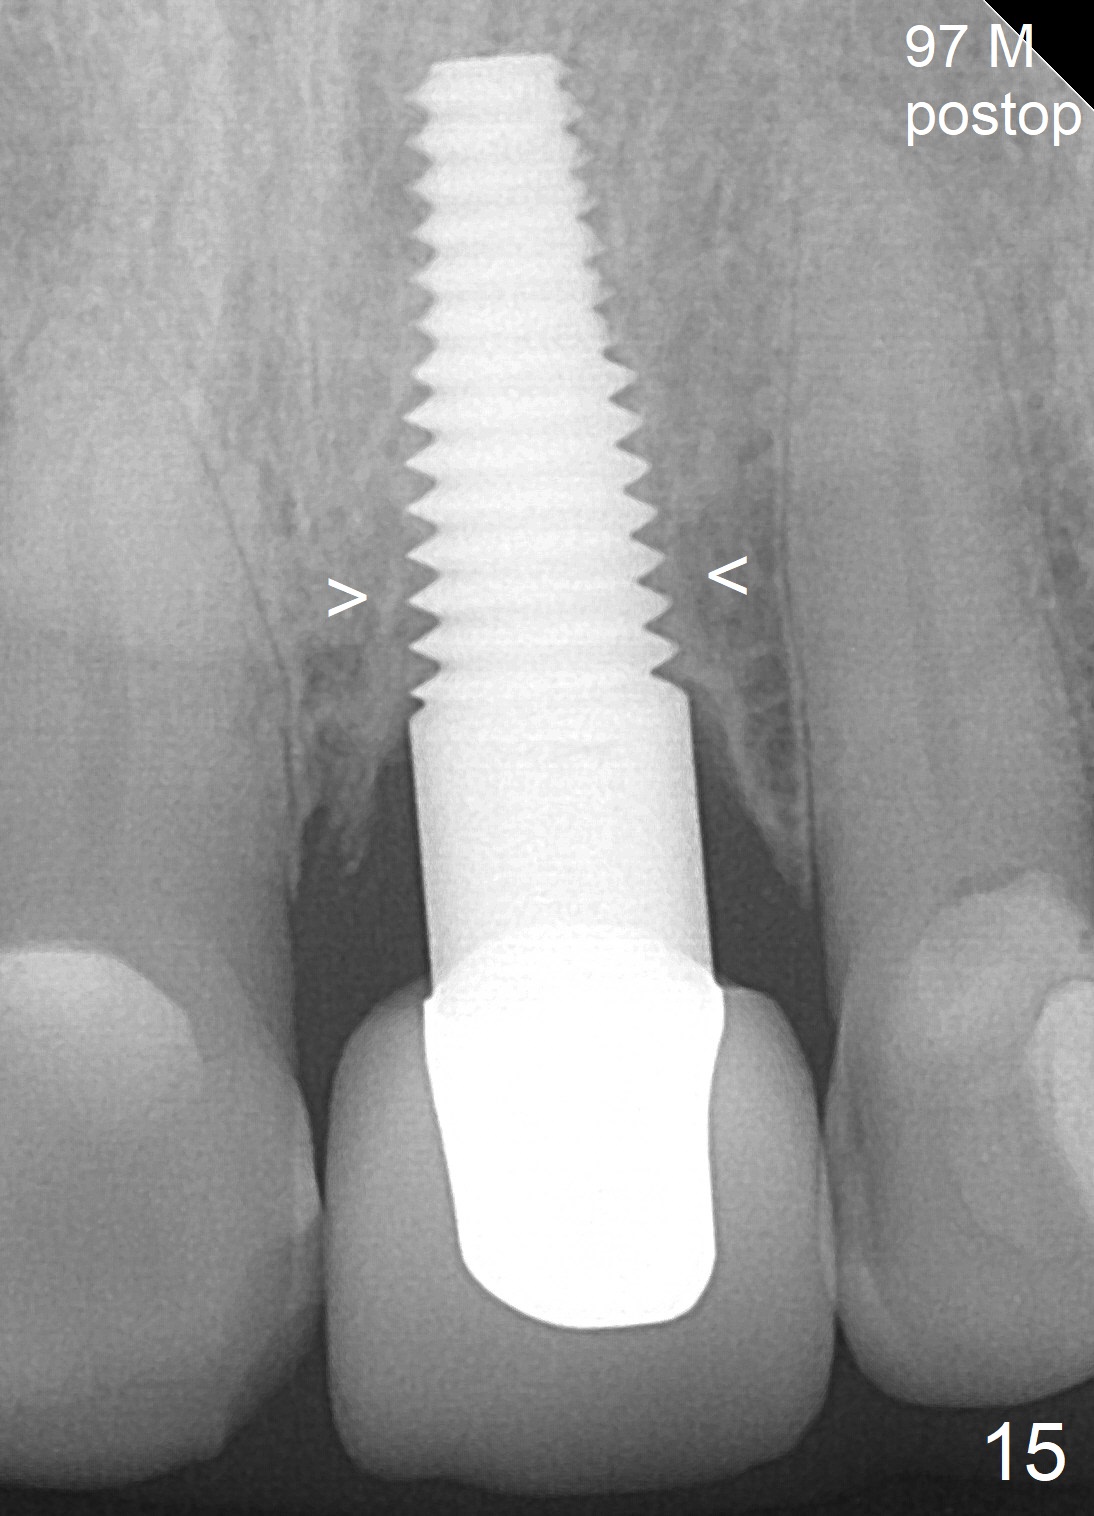

Fig.15: 97 months postop (2.5 years post cementation). The cortical bone extends apically along implant threads (<).